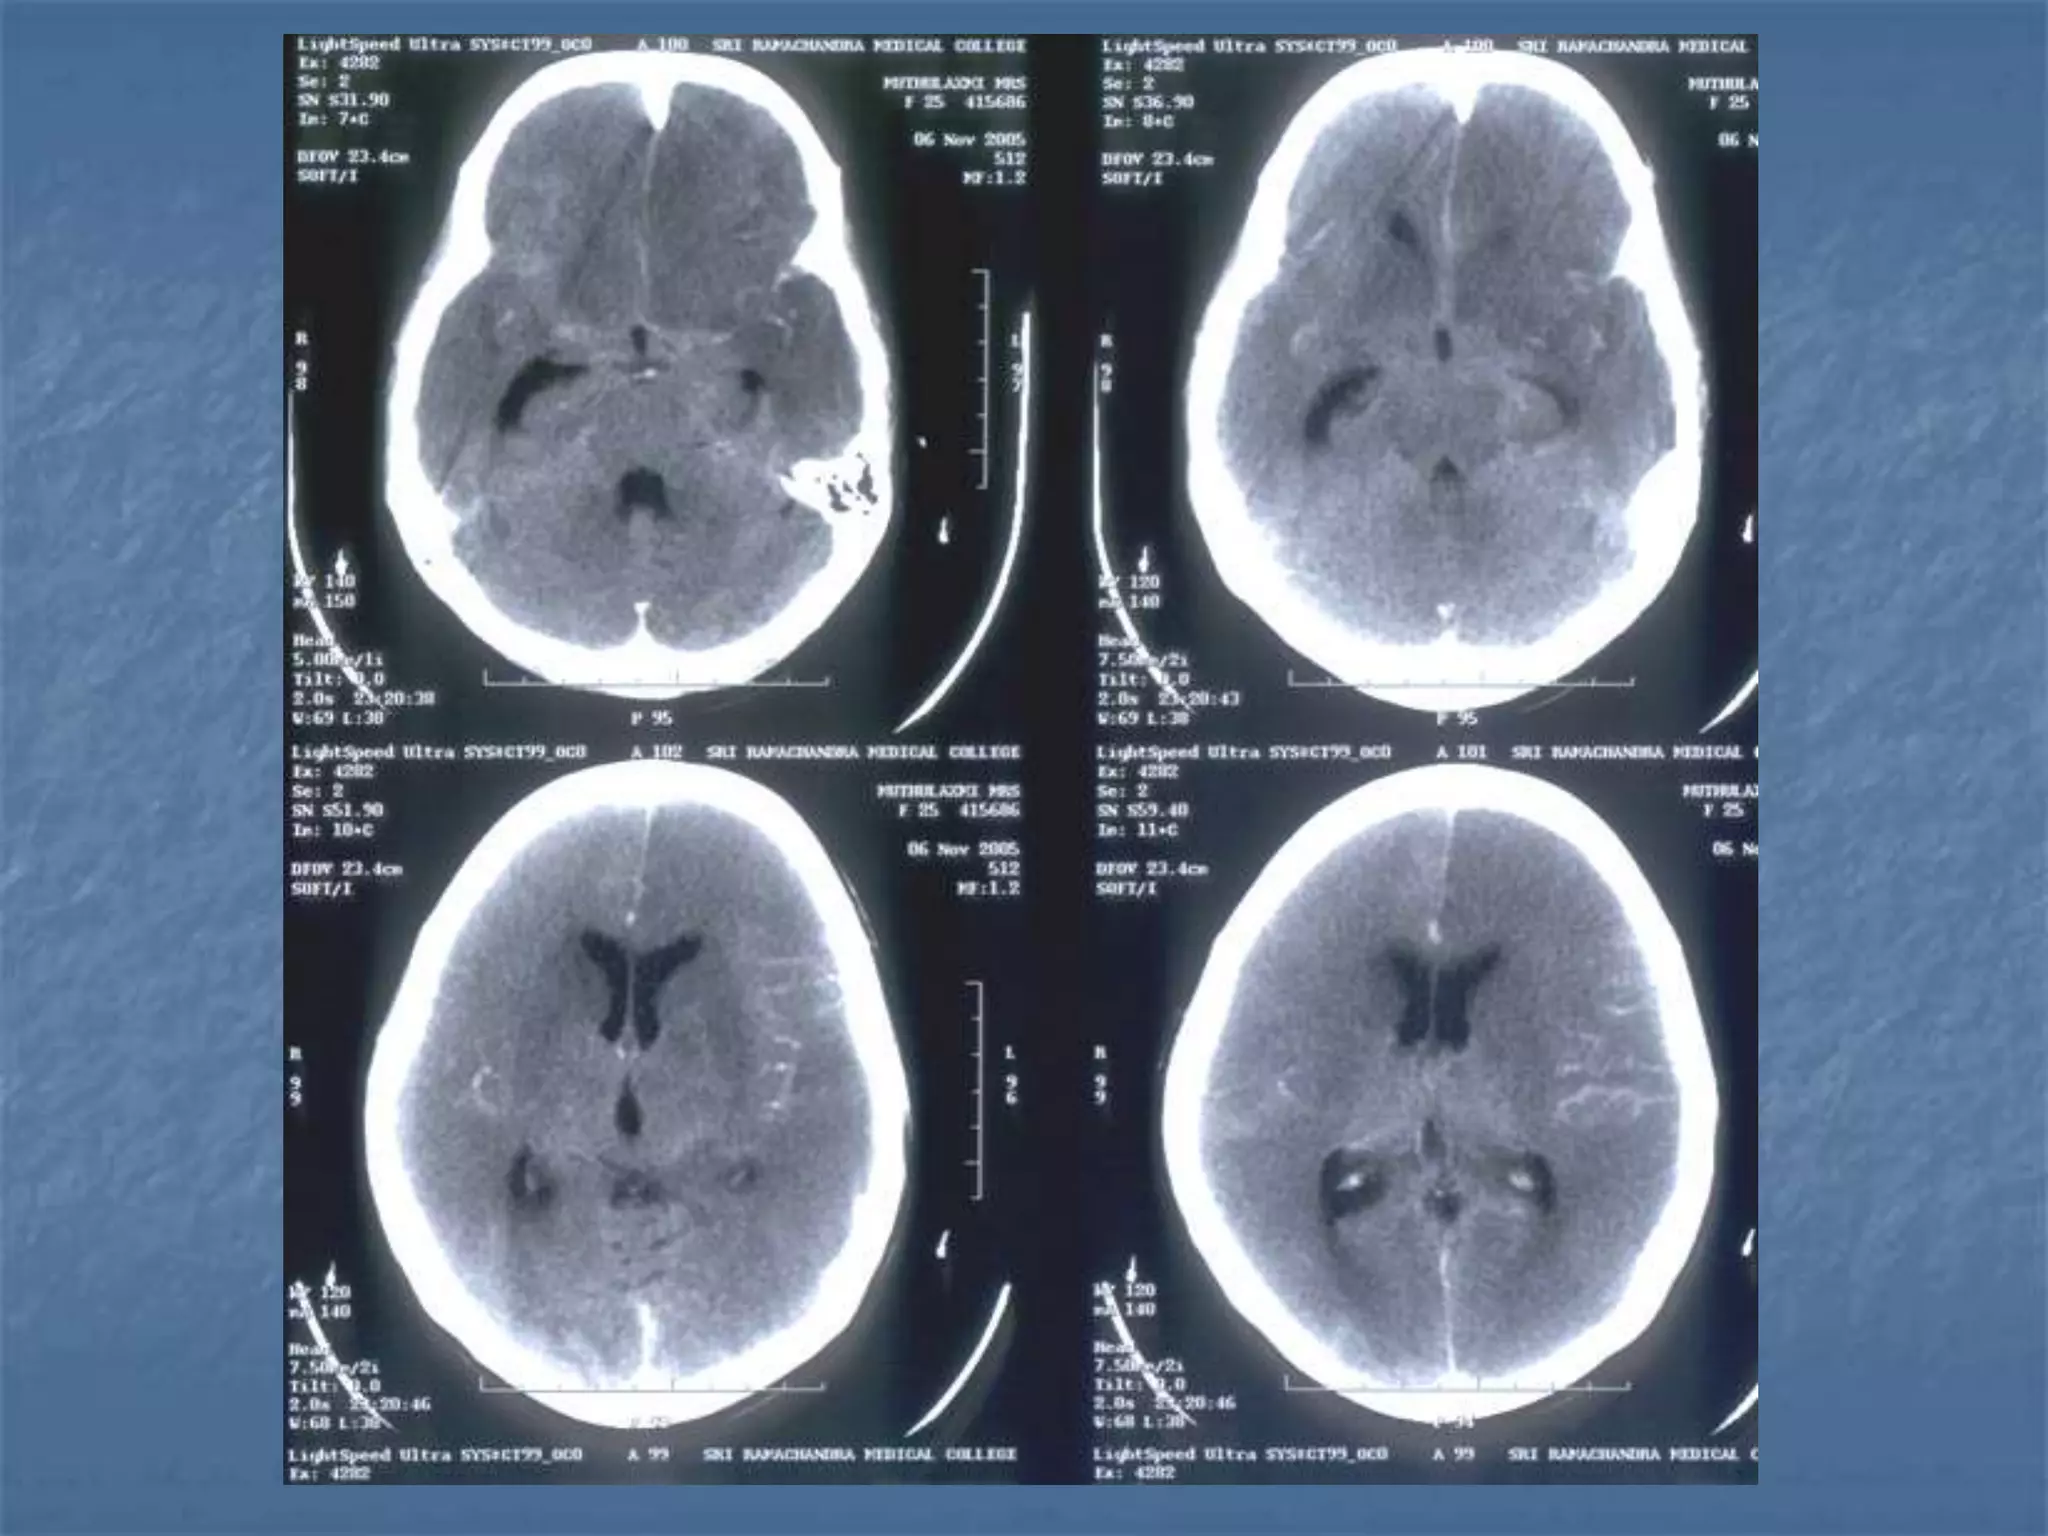

CONTUSION SAH

Hypertensive Hemorrhage

 Hypertensive hemorrhage accounts for

approximately 70-90% of non-traumatic primary

intracerebral hemorrhages. It is commonly due to

vasculopathy involving deep penetrating arteries

of the brain. Hypertensive hemorrhage has a

predilection for deep structures including the

thalamus, pons, cerebellum, and basal ganglia,

particularly the putamen and external capsule.

Thus, it often appears as a high-density

hemorrhage in the region of the basal ganglia.

Blood may extend into the ventricular system.

Intraventricular extension of the hematoma is

associated with a poor prognosis.